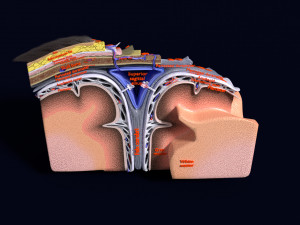

A blend model of brain along with its covering layers (meninges), skull bone and scalp labelled in detail and anatomically precise. The parts depicted are white, gray, pia, arachnoid, dura, bone, skin, fat, aponeurosis, periosteum, falx cerebri and more.

The material is high resolution image textures and normal maps based on non overlapping UVs. The texture and normal maps are packed with the blend file itself.